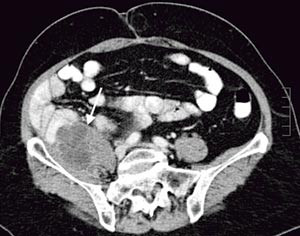

Pasienten. En tidligere frisk kvinne ble som 68-åring operert for cancer coeci med perforasjon. Det forelå en perikolisk abscess, og det ble gjort høyresidig hemikolektomi med reseksjon av fremre bukvegg. Inngrepet ble ansett som radikalt. I operasjonspreparatet fant man spredning til regionale lymfeknuter (Dukes C), og hun fikk derfor adjuvant kjemoterapi med 5-fluorouracil/leukovorin i seks måneder. Ett år senere utviklet hun sterke smerter i høyre flanke med utstråling til høyre lår, og ved CT ble det påvist en 12 cm stor tumor som infiltrerte m. iliopsoas dexter, oppfattet som et lokoregionalt residiv (fig 1). Det var ingen fjernmetastaser. Residivet ble resecert i muskulatur ved laparotomi, men tumorvev måtte etterlates omkring iliacakarene. Svulsten omsluttet n. femoralis, som måtte deles. Tumorsengen ble markert med metallklyper, og en brystprotese i silikon ble lagt på reseksjonsflaten for å skyve tynntarmen vekk fra det påtenkte strålefeltet (fig 2). Postoperativ CT viste likevel en interponert tarmslynge mellom protesen og fremre bukvegg (fig 3). Seks uker etter inngrepet ble det påbegynt radiokjemoterapi med 2 Gy x 25 som to motgående skråfelt og strålesensibiliserende 5-fluorouracil/leukovorin (fig 3). Under bestrålingen utviklet kvinnen høyresidig bekkenvenetrombose, og hun fikk antikoagulasjonsbehandling. Radioterapien var ledsaget av periodevise buksmerter, men uten diaré eller andre tegn til akutt stråleenteritt. Åtte uker etter endt bestråling ble hun igjen laparotomert. Den nevnte tarmslyngen frembød da ganske uttalte stråleskader. Protesen lot seg fjerne, i hovedsak ved stump disseksjon (fig 4). Pasienten ble likevel påført en ureterskade, som kunne repareres umiddelbart. Det var ingen gjenværende tumor, verken makro- eller mikroskopisk.